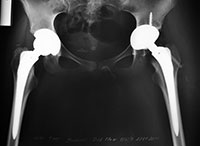

Оле 16 лет, она из г. Белгорода. Оля ребенок-инвалид, ее диагноз – двусторонний коксартроз, двусторонний гоноартроз, стероидный остеопороз. В ГУ «Российская детская клиническая больница» по медицинским показаниям ей должны установить 2 эндопротеза тазобедренного сустава Aesculap Bicontact (Германия). Стоимость 2-х эндопротезов составляет 271720 рублей.

Оплата эндопротезов за счет бюджетных средств не производится. Родители Оли не в состоянии самостоятельно оплатить эндопротезы. Мама работает преподавателем в Белгородской государственной специальной библиотеке для слепых, отец - электромонтером в ООО «Элпрон». Пенсия и выплаты ребенку-инвалиду составляет 7958 рублей в месяц.

Родители Оли и Главный врач ГУ РДКБ Н.Н.Ваганов обратились в фонд с просьбой о помощи в обеспечении операций по установке эндопротезов тазобедренного сустава Aesculap Bicontact (Германия). Стоимость высокотехнологичных операций, необходимого медикаментозного обеспечения и последующей реабилитации оплачивается за счет бюджетных средств. К сожалению, бюджетом не оплачивается стоимость эндопротезов, поэтому операции состоятся только при условии привлечения необходимых благотворительных средств.

Операции Оле будут проведены в рамках совместного высокотехнологичного инновационного проекта ГУ «Российская детская клиническая больница» и Благотворительного фонда помощи «Милосердие – детям» по эндопротезированию тазобедренных суставов детям-инвалидам, проходящим лечение в Российской детской клинической больнице, эндопротезами Aesculap Bicontact (Германия).